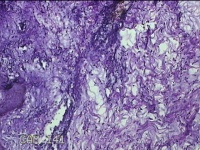

右腋下结节

性别

男

年龄

37岁

临床诊断

腋窝乳糜囊肿

一般病史

发现右腋下结节1年余,近日出现局部红肿及疼痛。

标本名称

大体所见

灰白暗红色组织2.7x1.8x0.8cm一块,表面带梭形皮肤2.8x1.3cm,皮下见结节2.7x1.3cm一个,切开结节呈实性,切面灰白粉红色,质软。

图2